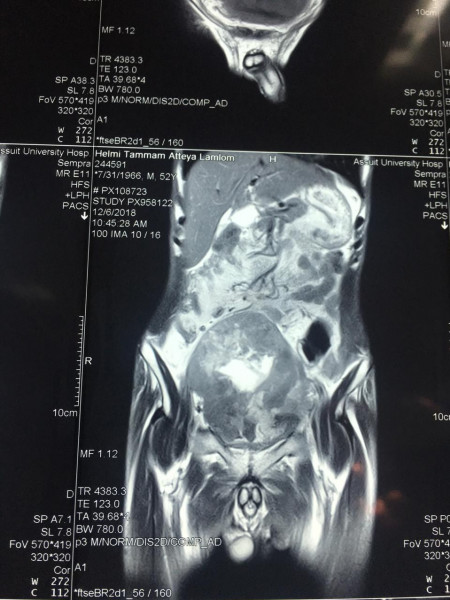

وعن تفاصيل العملية فقد أوضح الدكتور ضياء عبد الحميد الأستاذ بقسم جراحة المسالك البولية والكلى ورئيس وحدة أورام المسالك وقائد الفريق الطبي المسئول عن العملية ، أن تلك العملية تعد من أخطر عمليات استئصال أورام المثانة البولية وذلك نظراً لكبر حجم الورم واختراقه للأمعاء والأنسجة المجاورة من الشرايين والعضلات ، مما يشكل خطورة بالغة على حياه المريض والذي تم تعرضه لظروف معينة تسببت في إهماله للمرض لعدة سنوات، مشيراً أن ذلك تم من خلال التنسيق والتعاون مع أعضاء قسم الجراحة العامة .